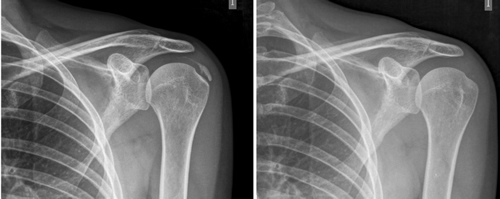

Fig. 5. Paciente mujer de 44 años, con tendinitis calcificante de supraespinoso izquierdo, de tipo resortivo, quien tras 20 sesiones de iontoforesis disminuyó el dolor medido por EVA de 10/10 a 4/10, y la calcificación de 22 mm a 0 mm (desaparición completa).